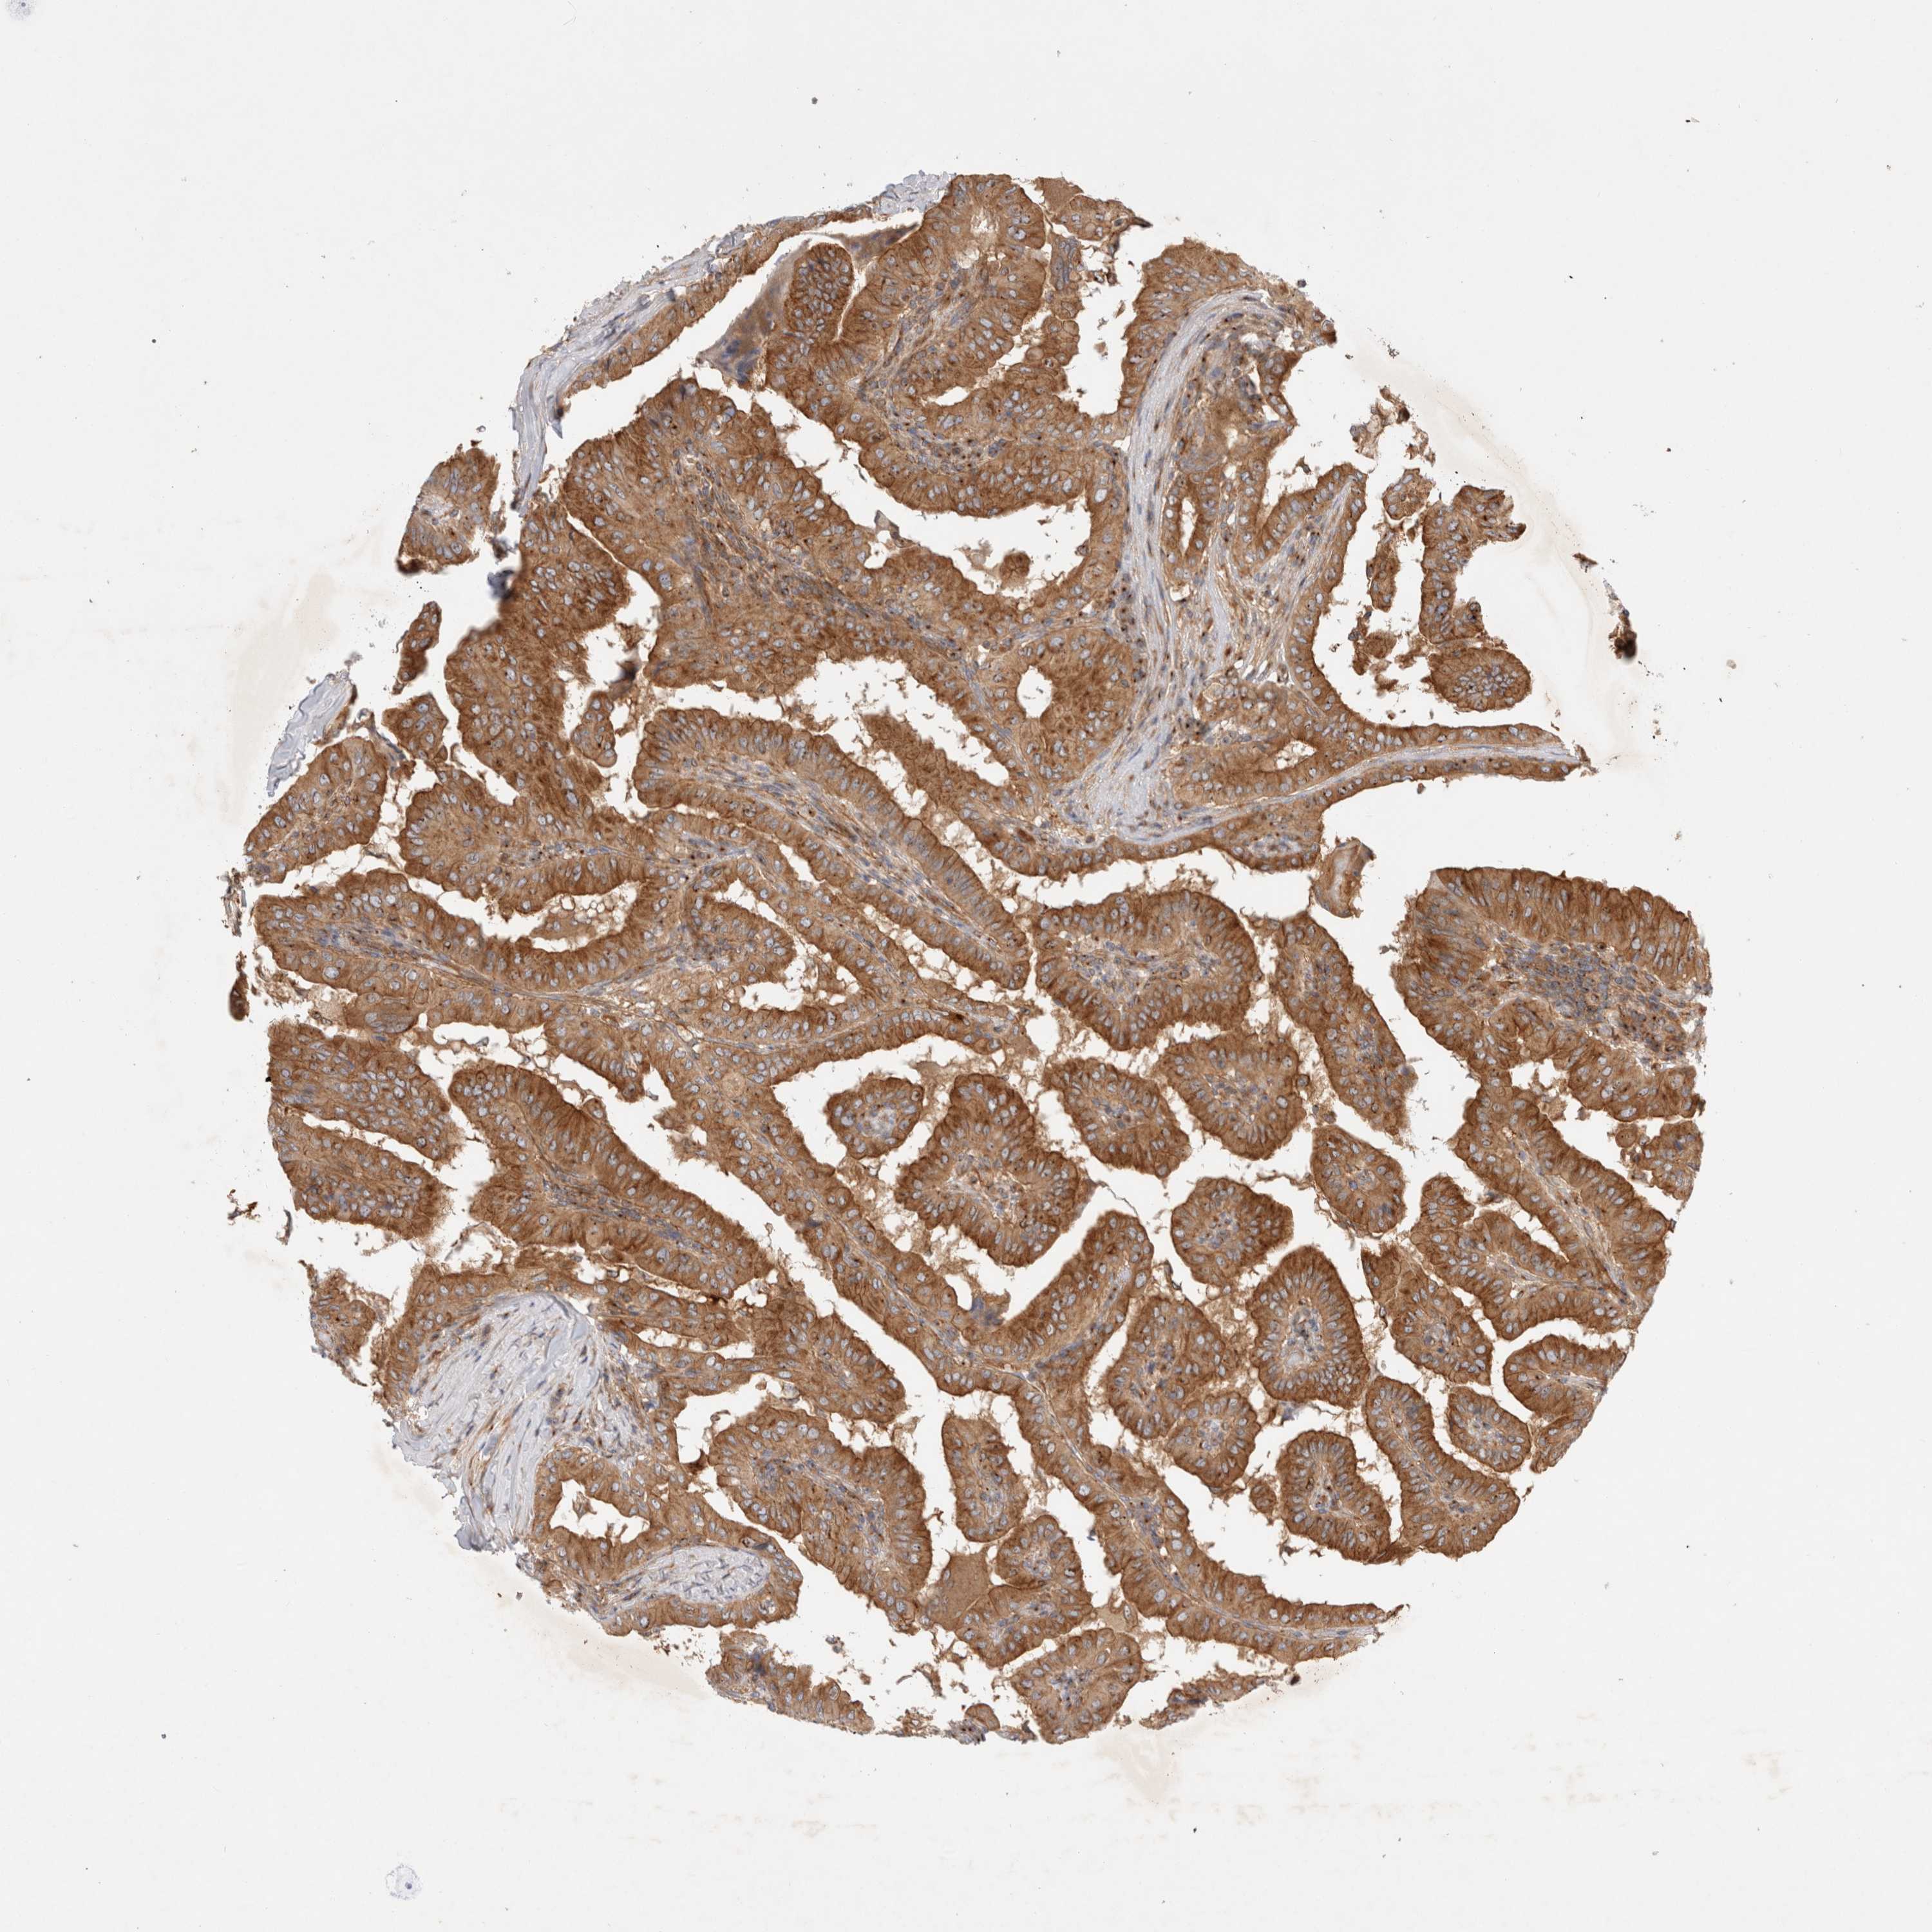

THYROID CANCER - Protein expressioni

A mouse-over function shows sample information and annotation data. Click on an image to view it in a full screen mode. Samples can be filtered based on level of antibody staining by selecting one or several of the following categories: high, medium, low and not detected. The assay and annotation is described here.

Note that samples used for immunohistochemistry by the Human Protein Atlas do not correspond to samples in the TCGA dataset.

Antibody stainingi

Antibody staining in the annotated cell types in the current human tissue is reported as not detected, low, medium, or high, based on conventional immunohistochemistry profiling in selected tissues. This score is based on the combination of the staining intensity and fraction of stained cells.

Each image is clickable and will lead to virtual microscopy that enables deeper exploration of all samples and also displays staining intensity scores, fraction scores and subcellular localization as well as patient and tissue information for each sample.

Antibody HPA026635

Staining

High

Medium

Low

Not detected

Intensity

Strong

Moderate

Weak

Negative

Quantity

>75%

75%-25%

<25%

None

Location

Nuclear

Cytoplasmic/membranous

Cytoplasmic/membranous,nuclear

Papillary adenocarcinoma, NOS

Follicular adenoma carcinoma, NOS